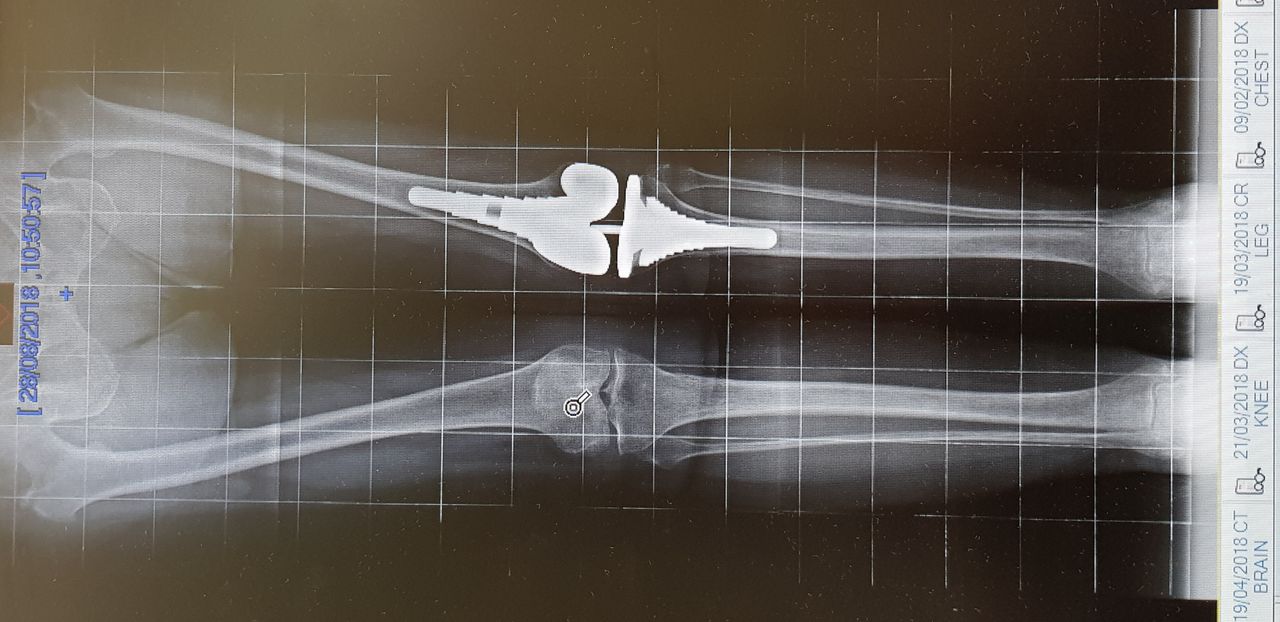

Da quando ha preso servizio presso l’Ospedale del Delta si è sempre occupato della chirurgia protesica del ginocchio sia monocompartimentale che totale acquisendo esperienza anche sulle tecniche basate sulla navigazione assistita che sull’impianto di protesi custom-made. Di routine esegue interventi di chirurgia artroscopica per il trattamento delle patologie meniscali e cartilaginee e di ricostruzione del legamento crociato anteriore mediante varie tecniche